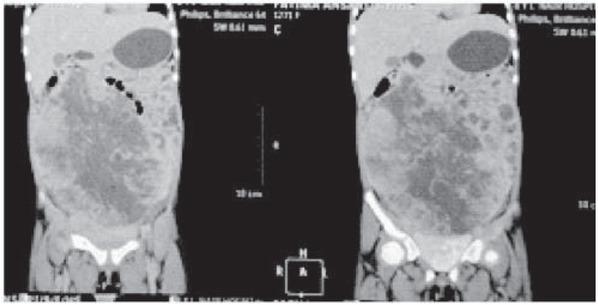

The girl was pale with massive abdominal distension and mild respiratory distress. A large 12 cm x 12 cm firm mass arising from the pelvis was palpable and occupied almost all of the abdomen. Blood investigations suggested anaemia. Lactate Dehydrogenase and Alpha-FetoProtein were raised (1143 U/l and more than 1000). Computed Tomography suggested a large solid cystic adnexal/ ovarian mass with septations and pedunculated serosal deposits on sigmoid colon and mild ascites suggesting neoplastic etiology (fig. 1 and 2).

Fig. 2

CT scan (Saggital section) showing large solid cystic adnexal/ovarian mass with septations and peritoneal deposits.